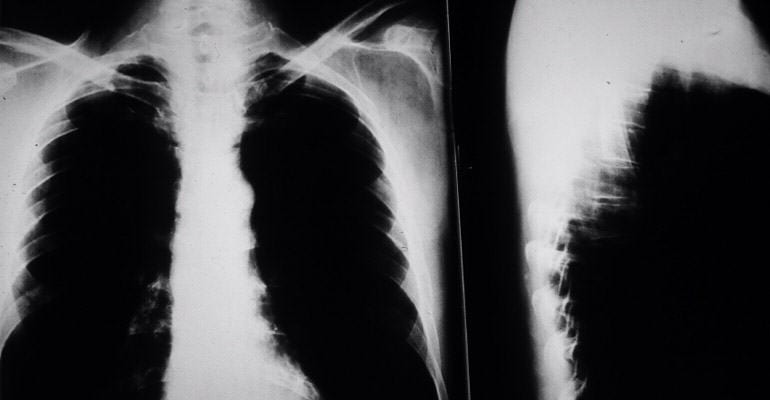

3 out of 4 cases of mesothelioma begin in the pleural mesothelium surrounding the lungs, but it can also begin in the abdominal cavity or around the heart.

Treatment options include surgery, radiation therapy, and chemotherapy, but mesothelioma is difficult to remove completely. This is because the cancer does not grow as a single tumor mass but spreads to nearby surfaces, nerves, and blood vessels.